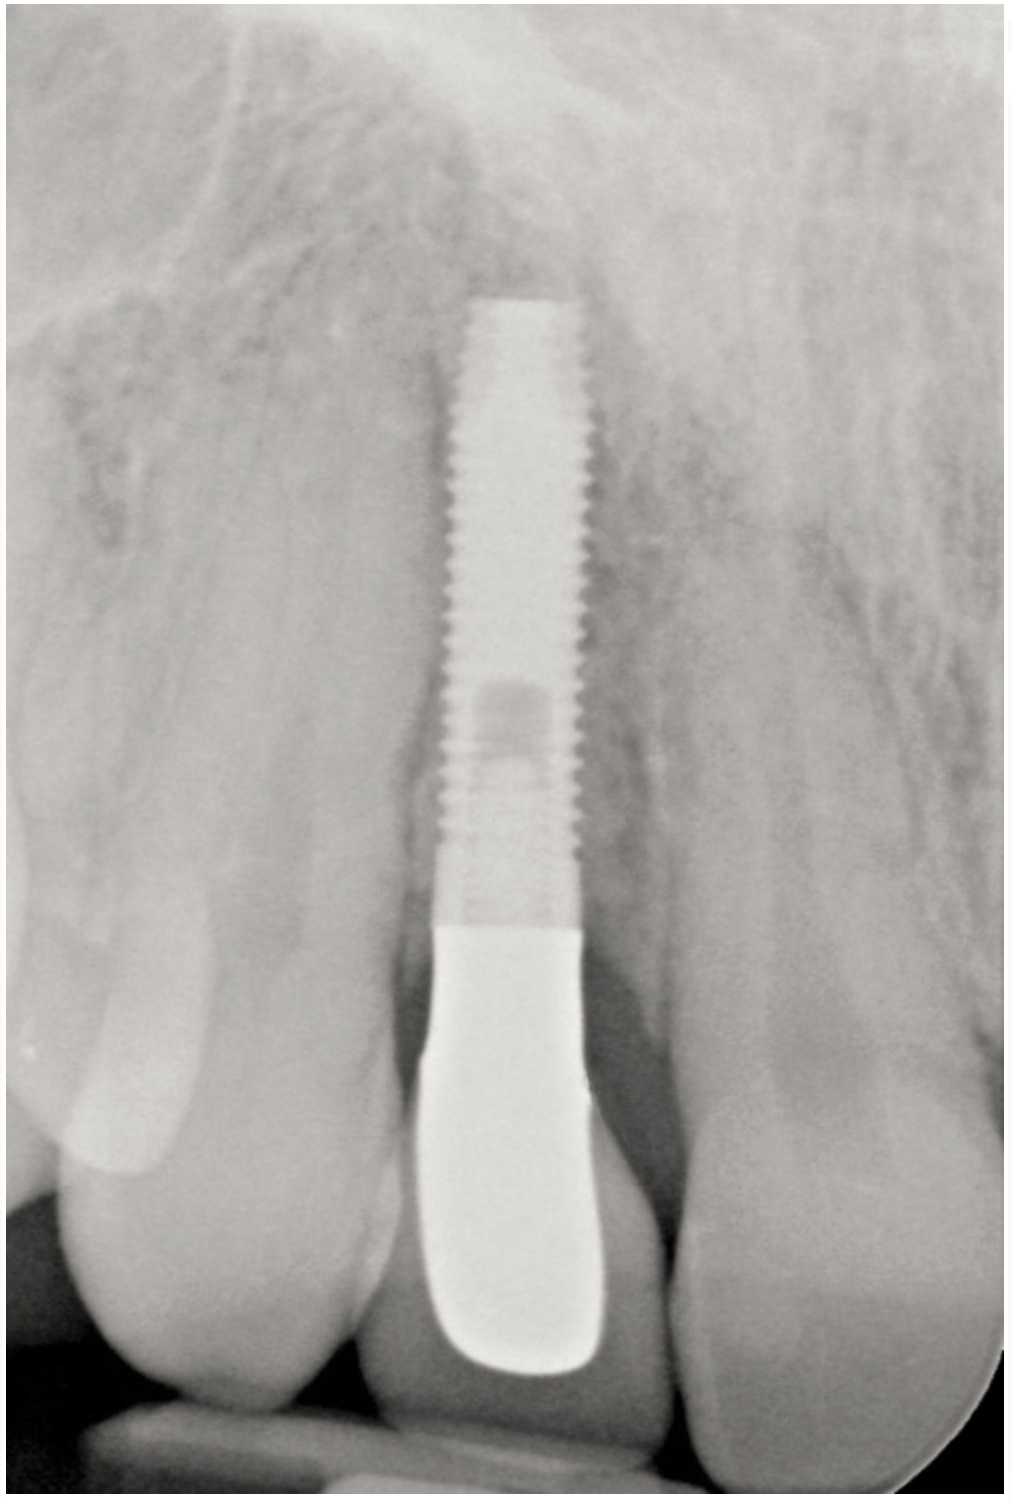

Fig 13. The final radiograph of the seated crown showing a healthy bone level around the implant.

Figure 13

Fig 17. Radiograph showed symmetrical infrabony defect affecting 50% of the implant surface.

Figure 17